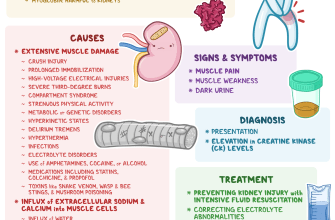

Rhabdomyolysis is a condition characterized by the